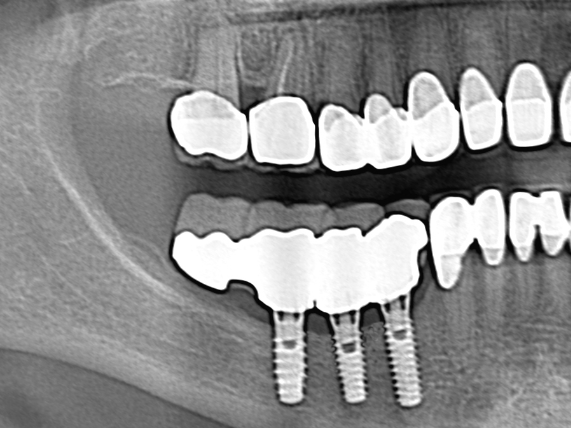

Inferior alveolar nerve lateralization and transposition in combination with the installation of dental implants is sometimes the only possible procedure to help patients to obtain a fixed prosthesis, in edentulous atrophic posterior mandibles. With careful pre-operative surgical and prosthetic planning, imaging, and extremely precise surgical technique, this procedure can be successfully used for implant placement in edentulous posterior mandibular segments.

In the above x-ray, you can see the mandibular nerve transposition and inserted implants in our patient.